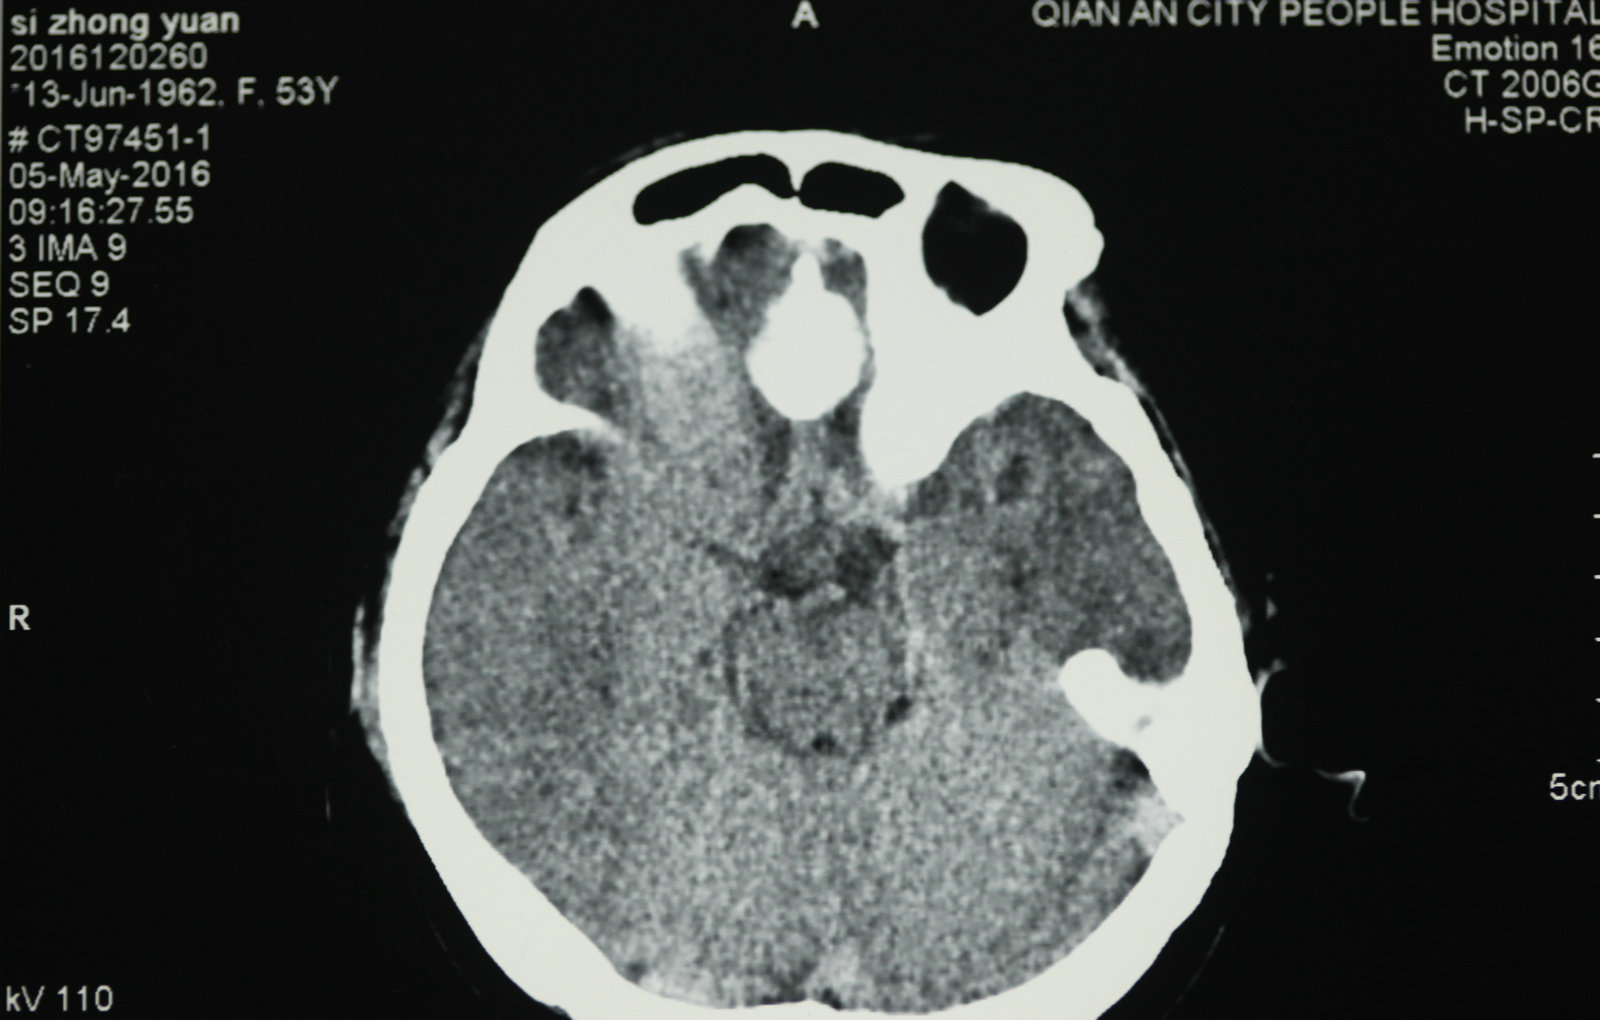

显微神经外科学是以应用手术显微镜为标志,但是,我们决不能片面的将显微神经外科学理解为只要手术中使用手术显微镜就是显微神经外科手术。而显微神经外科学的正确概念,足指以近代影像学为诊断基础,一整套与显微手术相匹配的手术设备、显微神经外科手术器械为保证的,以颅内病灶为中心的手术。显微神经外科学不仅是技术,更重要的是概念的更新。

1.以病灶性为中心手术,减少脑组织损伤:显微神经外科手术将经典神经外科“脑叶范围手术”,推向“病灶性手术”水平,尽量减少干扰脑组织,探索出新的手术入路。譬如,翼点入路、经岩骨入路以及额眶颧入路,这些具有代表性显微手术入路的共同特点是,牺牲部分颅底骨结构获得手术空间,经过脑外抵达病灶,尽量减少对脑的牵拉和损伤。20世纪70年代,Yasargil提出利用颅内自然的解剖间隙和经脑外到达病灶部位,处理病变,降低手术创伤,成为了显微神经外科手术的基本概念。随着对脑功能认识的逐步深入,手术中还对各种神经和脑血流进行监测,加大了对脑和神经的功能保护。